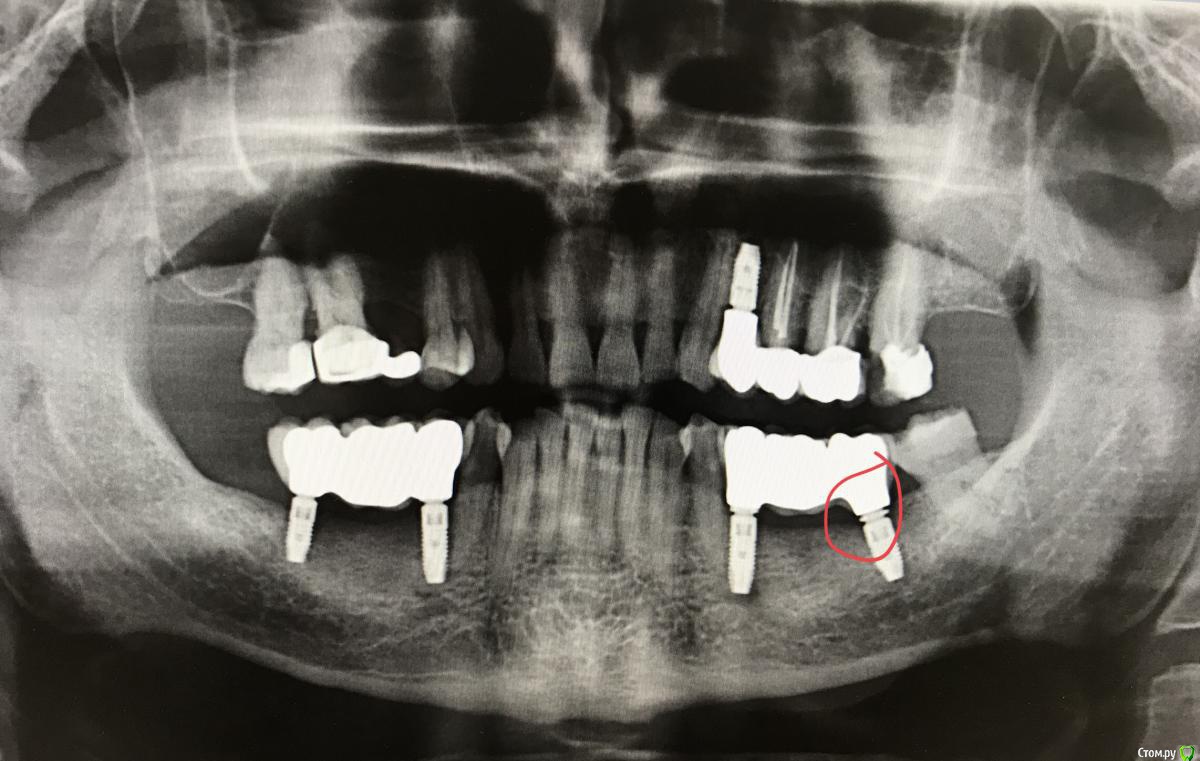

anvladd Опубликовано 20 марта, 2018 Поделиться Опубликовано 20 марта, 2018 Коллеги чем может грозить вот это? Технический косяк?Пилил много по прикусу,мост сел норм,щелей между десной и коронками нет. Импланты ASTRA Ссылка на комментарий

makinos Опубликовано 20 марта, 2018 Поделиться Опубликовано 20 марта, 2018 Если работу недавно сдали, значит модель в клинике еще. Откручивайте и в лабу, пусть все расклеивают). Добавят керамики, которую вы спилили и вклеют по-людски. Там на 35 тоже не все гладко, по-моему. Так оставлять- не вариант. 3 Ссылка на комментарий

RuStom Опубликовано 21 марта, 2018 Поделиться Опубликовано 21 марта, 2018 а что за титановые основания?такое впечатление, что там просто шестигранник без конуса? Ссылка на комментарий

RuStom Опубликовано 21 марта, 2018 Поделиться Опубликовано 21 марта, 2018 и про титановые основания спросите. просто интересно даже.вот снимок коронки на Астре с оригинальным абатментом. там видно, что вокруг "ножки" винта практически нет саободного пространства. все заполнено конусом и шестигранником.http://forum.stom.ru/uploads/monthly_12_2017/post-16178-0-06922300-1514347921_thumb.jpg на Вашем снимке же очень много пространства вокруг винта... Ссылка на комментарий

Борис80 Опубликовано 23 марта, 2018 Поделиться Опубликовано 23 марта, 2018 кость не мешает абатменту и коронке? Ссылка на комментарий